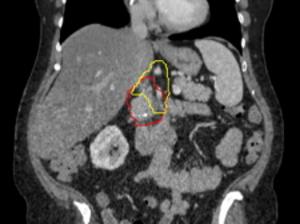

Image of a what is targeted with radiation. Red represents the pancreatic tumor, which is contacting with a major nearby...Johns Hopkins Medicine